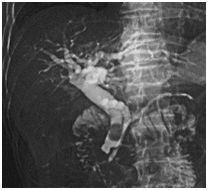

Figure 3 Ascaris infection.

Ascaris lumbricoides (Figure 3)